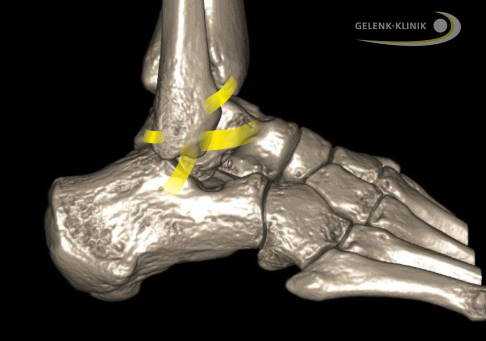

Внешние связки соединяют малоберцовую кость (Fibula) с пяточной и таранной костями. Межберцовый синдесмоз проходит между большеберцовой и малоберцовой костями. © Gelenk-Klinik

Причинами разрыва связок лодыжки зачастую являются падения либо травмы во время занятий спортом. Связки теряют свою стабилизирующую функцию, и пациенты больше не могут двигаться как раньше. Чаще всего повреждениям подвержены внешние связки. Передняя таранно-малоберцовая связка травмируется почти при всех повреждениях латеральных связок.